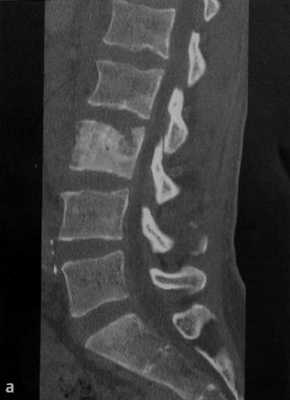

а-с Женщина 38 лет с анапластической неходжкинской лимфомой и вторичным поражением 1.3. (а) 16-срезовая КТ, сагиттальная реконструкция. Преимущественно склеротическая плотность поражения с компрессией позвонка, поражающей верхнюю замыкательную пластинку;

(b) Т1-взвешенная последовательность. Диффузное снижение МР-сигнала от костного мозга пораженного позвонка по сравнению с МР-сигналом от костного мозга здоровых позвонков. Инфильтрация тела позвонка выражена менее интенсивно в сравнении со здоровым костным мозгом,

с Т2-взвешенная последовательность. Гипоинтенсивный сигнал 1.3 вследствие формирования новой кости.